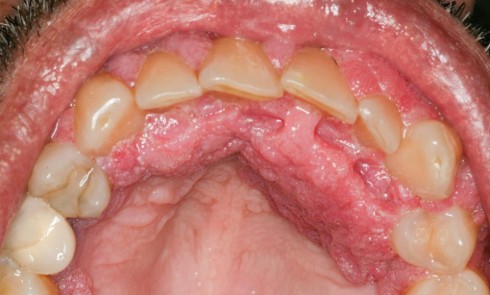

Anamnèse Une patiente de 29 ans, sans antécédent médical rapporté et non-fumeuse, consulte pour une inflammation gingivale persistante, malgré plusieurs...